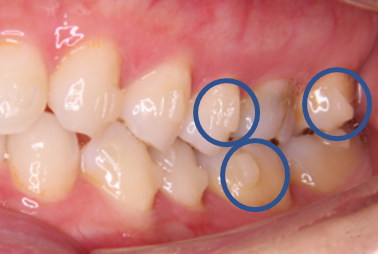

写真で見ると、こんな感じです↓↓↓

インビザライン矯正を実際にスタートするにあたり、まず行うこととして、アタッチメントと呼ばれる歯の表面にレジンの突起物を付けます。

これを付けることで、歯に加わる力を調整し、歯を効率的に動かすことができます。

アタッチメントには、実は様々な形状があり、歯を動かしたい場所や動かし方によって、形状、数、場所が変わってきます。

どこの場所にどのような形のアタッチメントを付けると、効率よく歯が動かせるのか、とても考えられているんです(*^^)v

しかも、白色なのでよく見ないと付いているのかもわからない程度で、